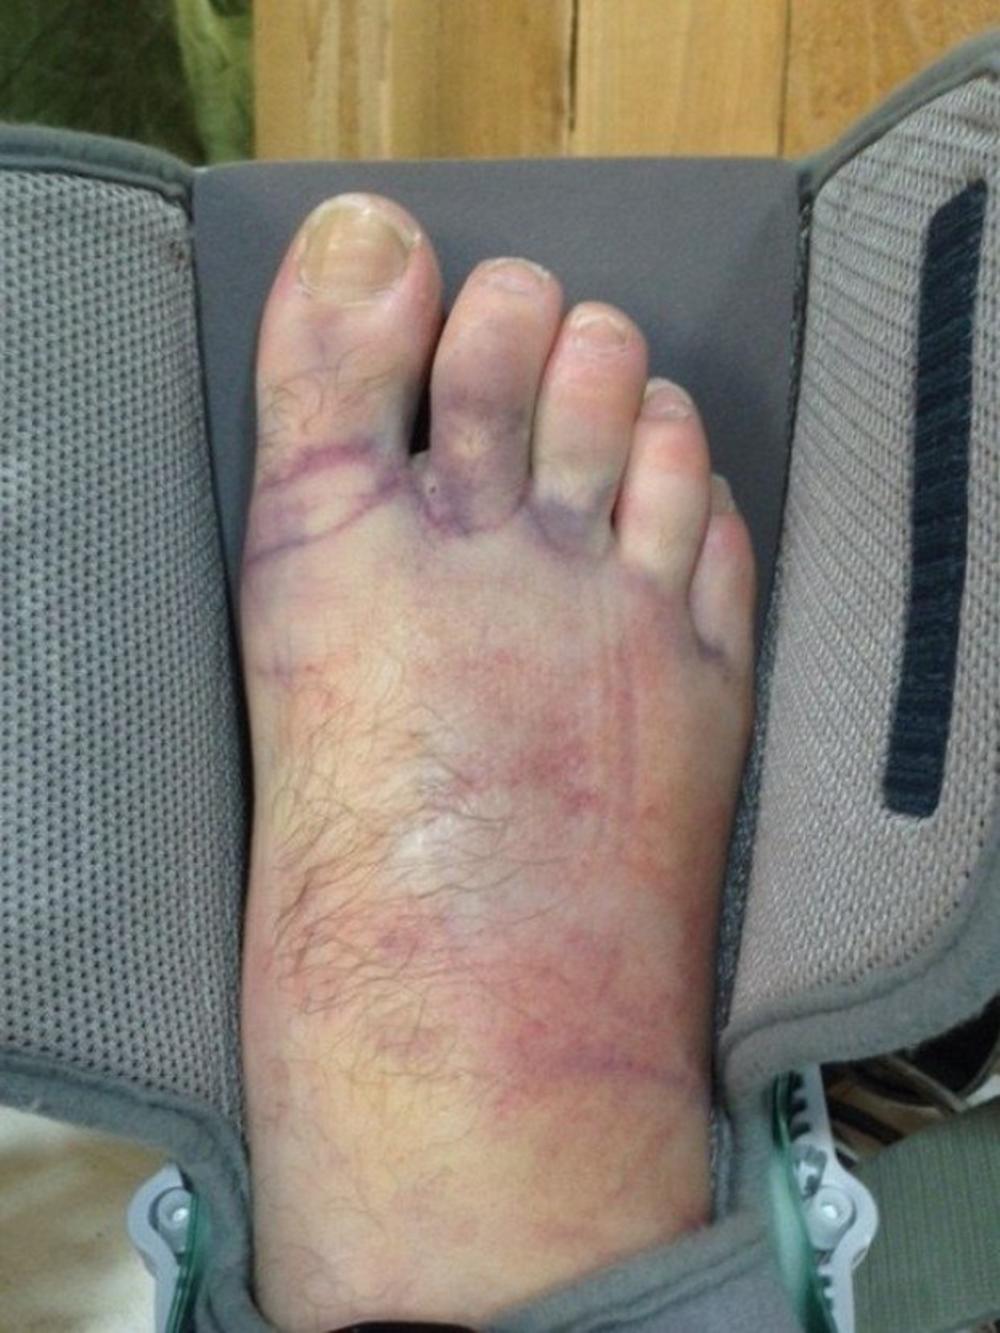

Istog trenutka otišao je kod hirurga koji ga je operisao.

Nakon ponovne intervencije, na površini je ostala mala rupa da podseća da je tu izronio šraf. Sada, dečko ponovo normalno hoda…